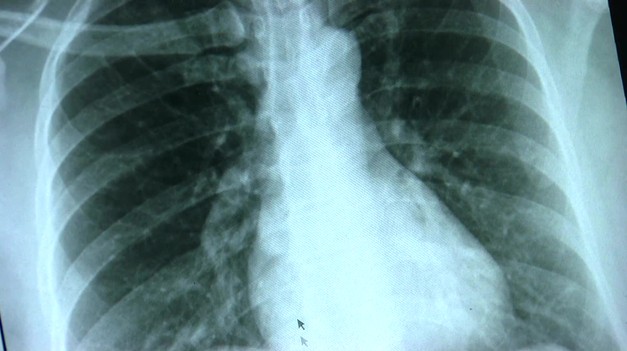

Nová lieková legislatíva: Minister Šaško sľubuje lepšiu dostupnosť liekov Maturity, uzatváranie známok a stres útočia na mozog. Neurologička radí, ako môžu rodičia pomôcť deťom zvládnuť náročné obdobie Sezóna kliešťov je tu, Jeden výlet do prírody môže mať trvalé následky! Čo spôsobuje kliešťová encefalitída a borelióza? Na lodi zabíjal kmeň hantavírusu Andes, ktorý sa prenáša aj z človeka na človeka Lekári varujú: Najväčšie mýty o opaľovaní vás môžu stáť zdravie Sepsa zabíja zdravých dospelých i deti do pár hodín: 5 príznakov, ktoré musíte poznať a okamžite konať